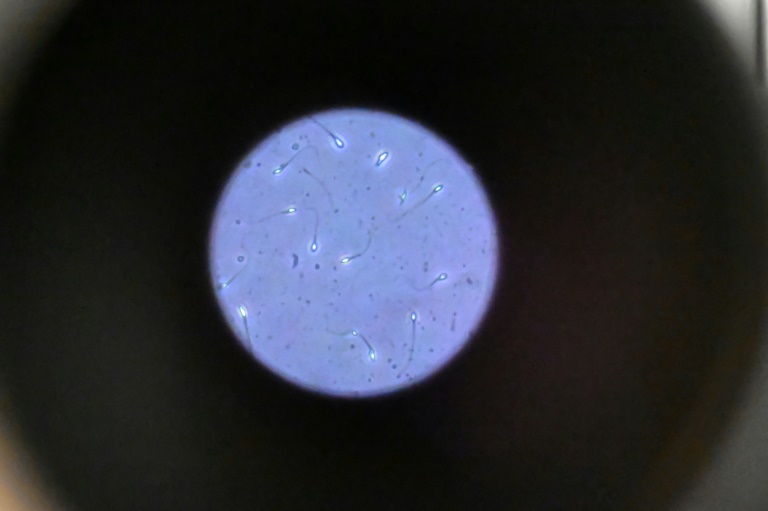

Retrouver l'origine des adultes nés de PMA: un travail de limier

Pour répondre à la demande d'adultes nés d'une PMA de connaître l'identité du donneur de gamète, les hôpitaux effectuent un travail de limier dans des archives conçues pour cacher ce précieux secret, une quête qui...

19/09/2025 AFP France